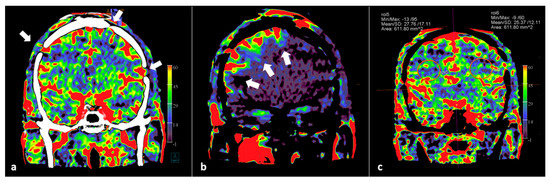

- Wen, L.-L.; Zhang, X.; Zhang, Q.-R.; Wu, Q.; Chen, S.-J.; Deng, J.-L.; Huang, K.; Wang, H.-D. Flat-detector computed tomography PBV map in the evaluation of presurgical embolization for hypervascular brain tumors. J. NeuroIntervent. Surg. 2017, 9, 1139–1144. [Google Scholar] [CrossRef] [PubMed]

- van der Zijden, T.; Mondelaers, A.; Franck, C.; Voormolen, M.; Menovsky, T. Selective Angiographic Flat Detector Computer Tomography Blood Volume Imaging in Pre-Operative Vascular Mapping and Embolization of Hypervascular Intracranial Tumors—Preliminary Clinical Experience. Diagnostics 2022, 12, 1185. [Google Scholar] [CrossRef] [PubMed]